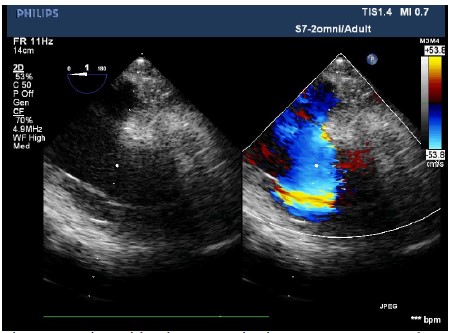

The patient entered the operating room and her ECG was monitored regularly. The induction of anesthesia was smooth. When the surgical team was manipulating the fracture, her blood pressure (BP) suddenly decreased to 63/43 mmHg, heart rate increased to 112 beats/min, and the saturation of pulse oxygen (SpO2) fell to 72%. 1 mg methoxamine was used to raise the blood pressure without success. 2 mg methoxamine, 6 mg ephedrine, and 8 μg nonadrenaline were subsequently given without significant blood pressure change. The central venous pressure was 15mmHg. In addition, the end tidal carbon dioxide decreased to 10 mmHg. There were no significant airway pressure changes. While an allergic reaction was initially suspected, no dermatological changes were identified. Emergency blood gas indicated a partial pressure of artery carbon dioxide (PaCO2) of 77.9 mmHg, and an oxygen partial pressure of 67mmHg. Potential pulmonary embolism was suspected. A transesophageal echocardiography (TEE) was followed. It revealed an enlarged right atrium (Figure1), hypokinesia of the free right ventricle wall, and poor filling of left ventricular. The ratio of left/right ventricular apparent disorder and the pressure of tricuspid valve was 51mmHg with massive regurgitation of 3.57m/s (Figure 2). Severe tricuspid reflux was also observed (Figure 3). Epinephrine and milrinone along with high-dose vasopressin were initiated. While no thrombi in the pulmonary or right ventricle were identified, unstable hemodynamics, changes in carbon dioxide, findings in TEE strongly suggested a possible major PE. Extracorporeal membrane oxygenation (ECMO) was immediately established and an emergent pulmonary thromboembolectomy was successfully performed. The patient was transferred to the surgical intensive care unit for monitoring and evaluation. The patient was discharged without residual deficits after 20 days in surgical intensive care unit.

Figure 1: Right atrial on 2D-transesophageal echocardiography. Enlarged RA and hypokinesia of the free right ventricle wall were observed.